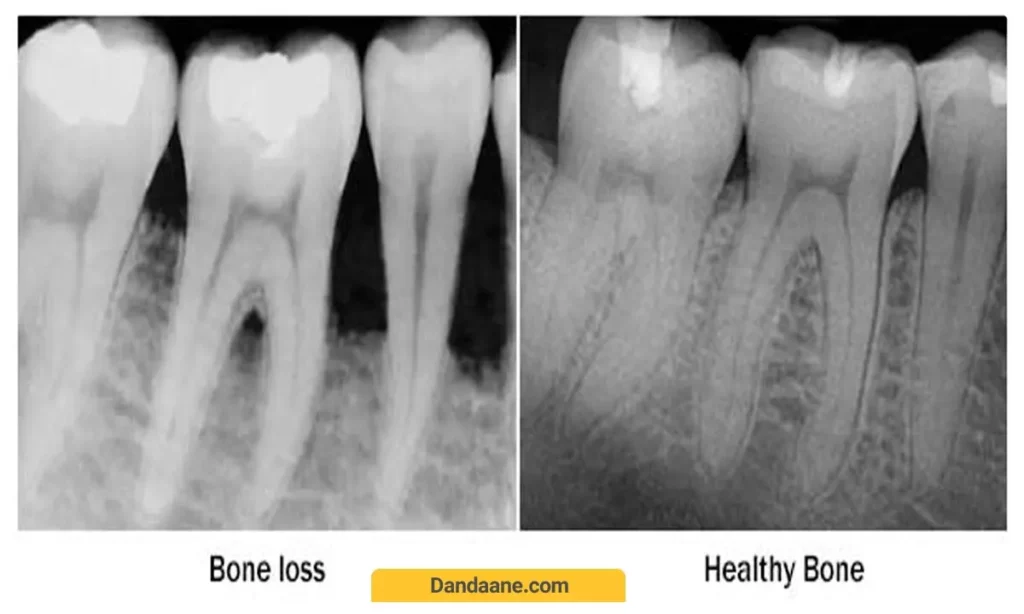

3.تحلیل استخوان

در حین جابجایی دندان ها، استخوان اطراف ریشه دندان تحلیل می رود و به تدریج ساخته می شود. این فرآیند ممکن است احساس لق شدن دندان در طول ارتودنسی می شود.